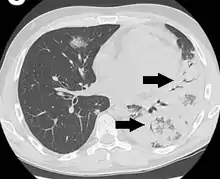

CT scan of air bronchograms in a case of legionnaires' disease.

An air bronchogram is defined as a pattern of air-filled bronchi on a background of airless lung.[1]